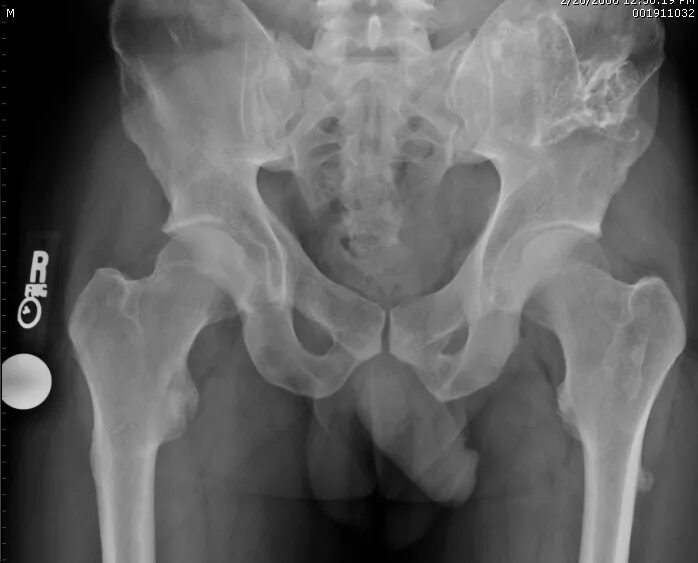

Метастазы в тазобедренном суставе